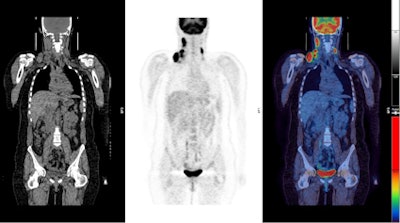

PET imaging was performed on full-ring PET or PET/CT scanners at centers within the U.K. National Cancer Research Institute (NCRI) PET Research Network. PET images were negative among 426 patients (75%). Individuals who had positive PET results continued on to receive additional radiotherapy.

Radford and colleagues randomly divided 420 of the PET-negative patients into two groups, some who received radiotherapy and some who did not. After ruling out some patients whose care didn't follow the study protocol (such as by receiving radiation therapy despite being assigned to the no-treatment group), they were left with a total of 392 patients.

Among these patients, PET-negative patients who received radiation therapy had a three-year progression-free survival rate of 97.1%, while the PET-negative individuals who received no treatment had a survival rate of 90.8%.